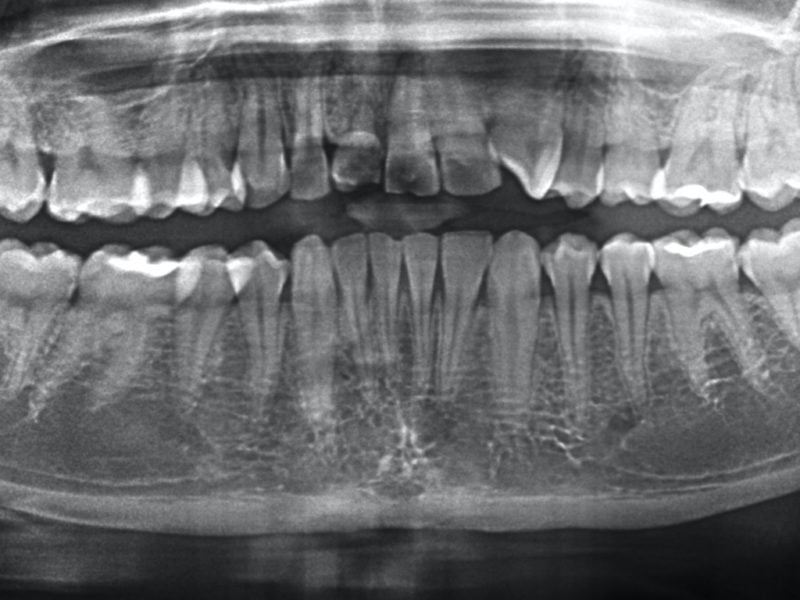

The patient came to our attention with a periodontal problem concerning element 1.1. After a radiographic check-up we confirmed a treatment plan that required the extraction of the tooth, the removal of the below cyst and the direct insertion of a slim implant in the same site. In order to maintain the soft tissues natural appearance we decided to perform some bone grafting. As the implant is in an aesthetically important position we inserted in a provisional tooth in same session.